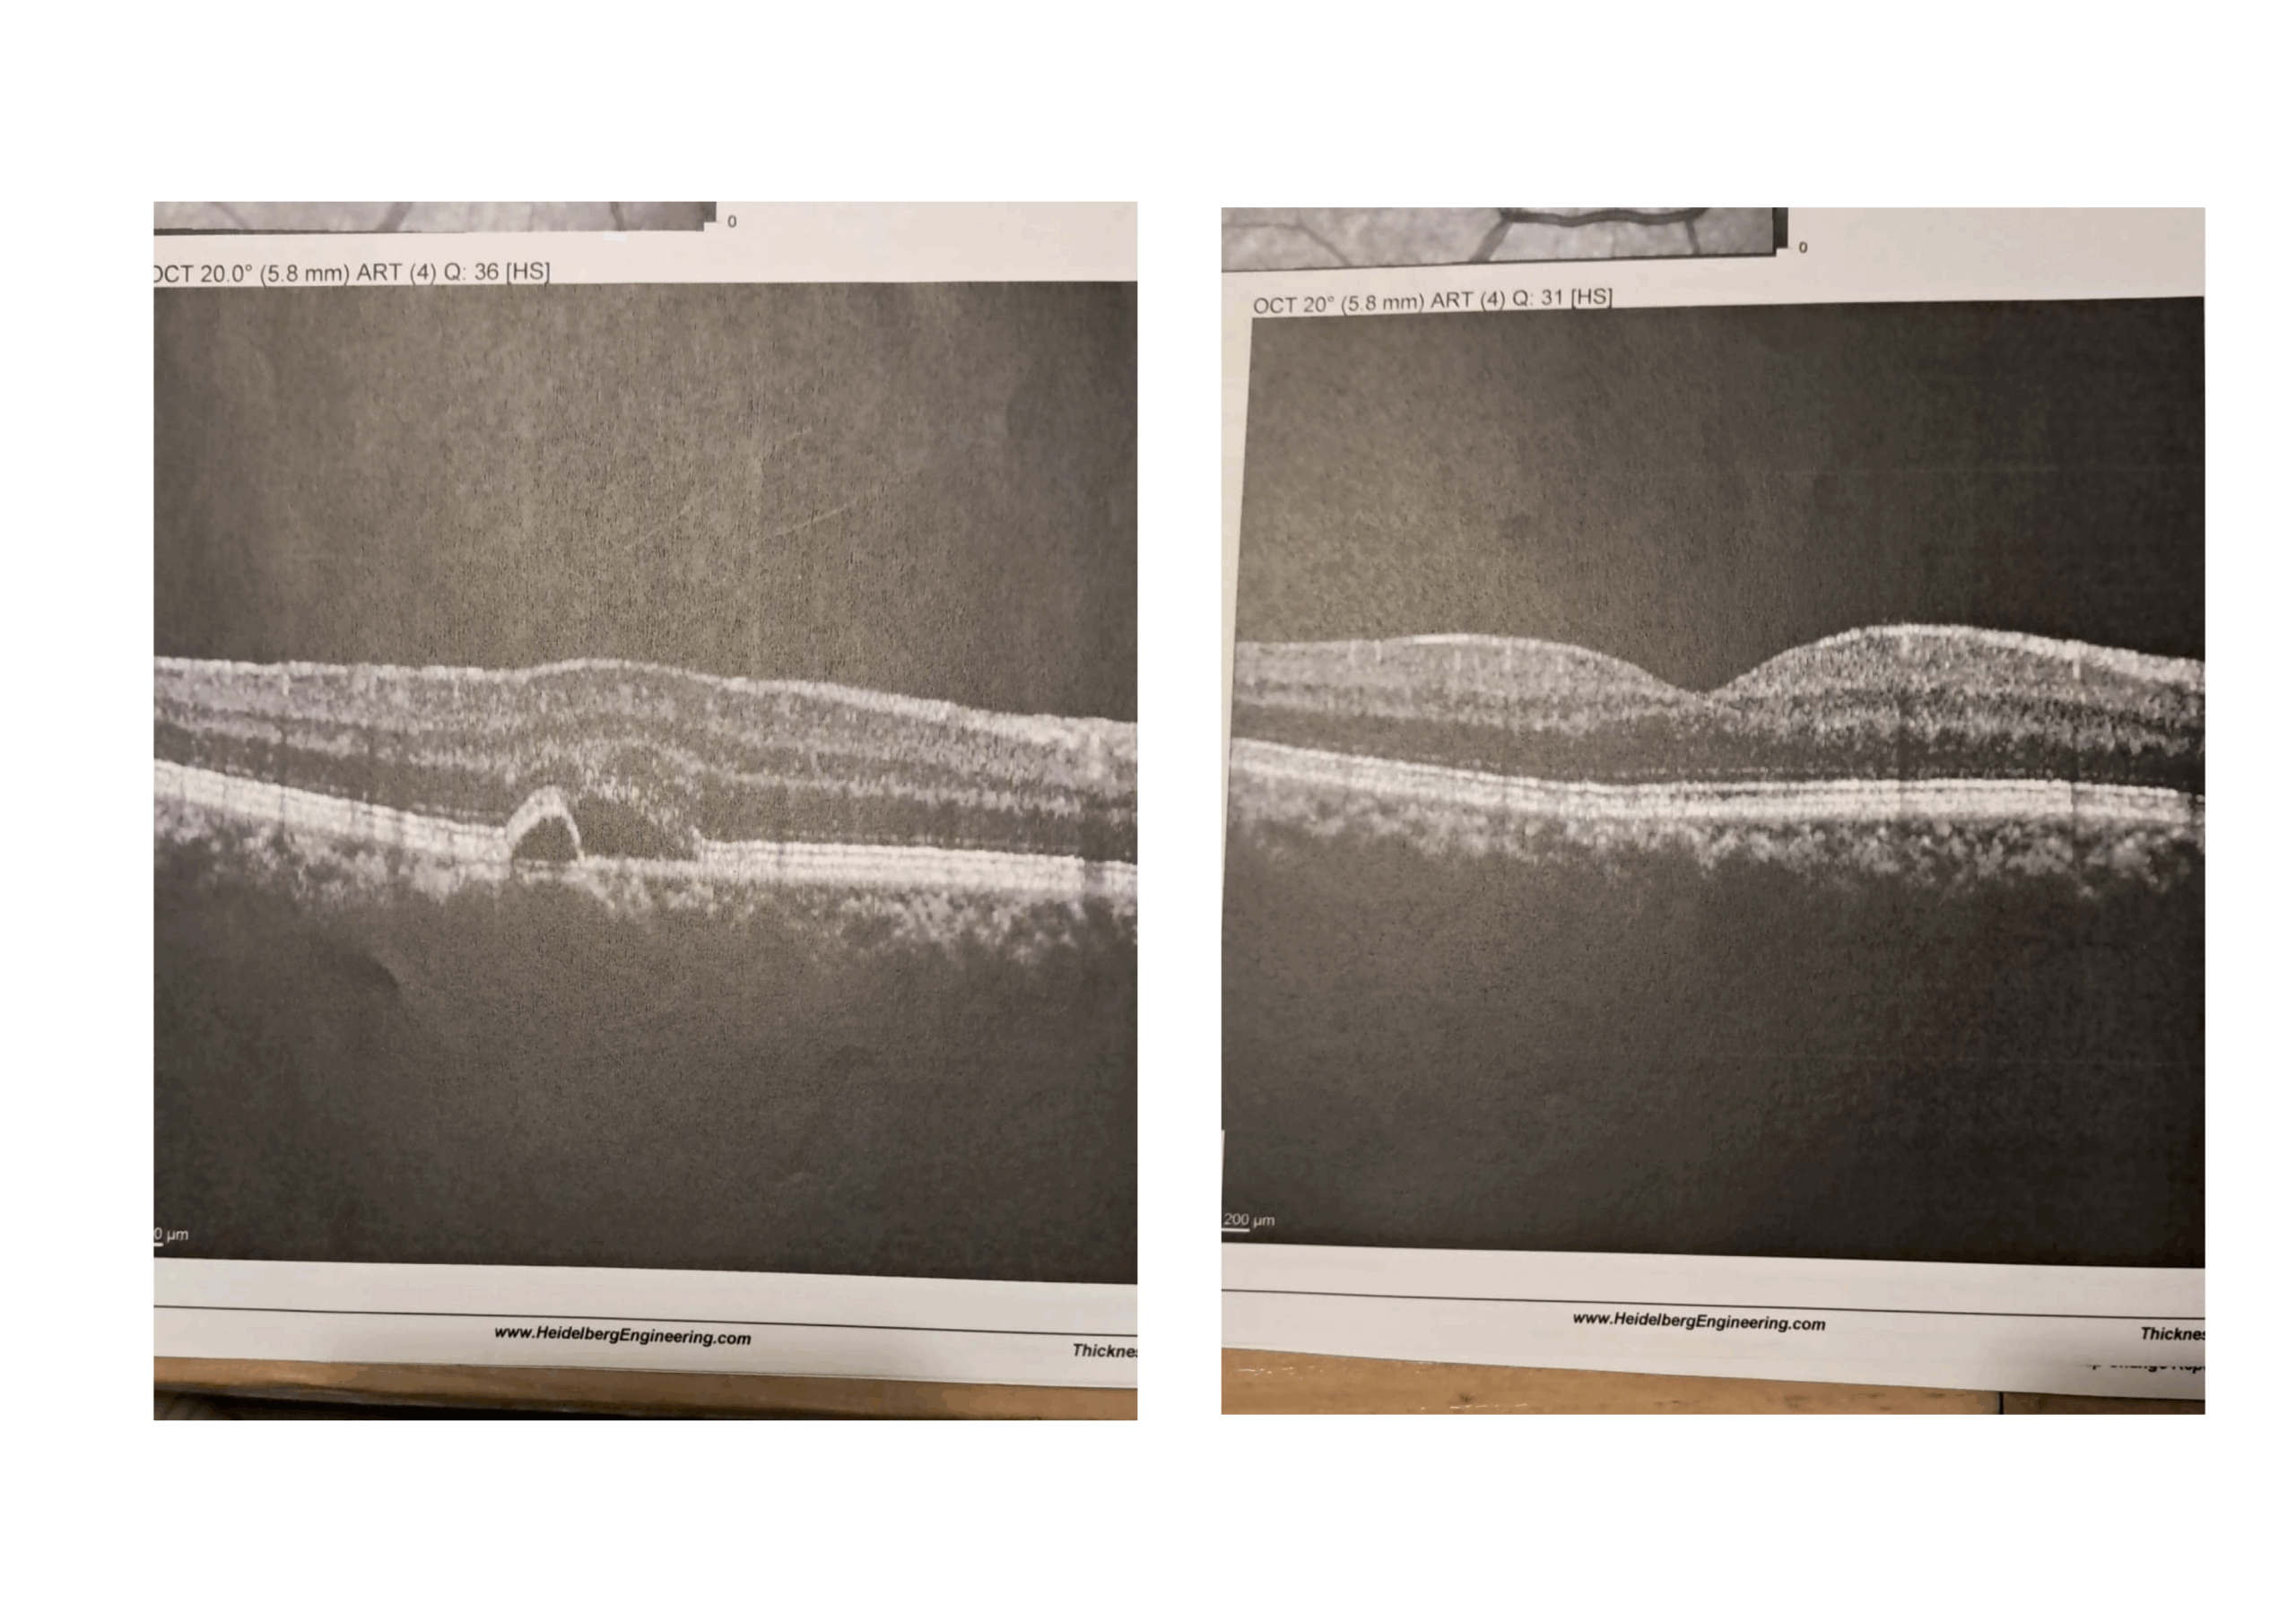

Ho iniziato a fare degli esami medici, i classici «OCT», per vedere cosa avevo, e ho scoperto di soffrire di «maculopatía», una malattia degli occhi sostanzialmente incurabile che è destinata nel lungo periodo a distruggere completamente la vista.

Se dunque a gennaio 2025, a séguito di altri fatti che mi avevano messo sotto pressione, la situazione ancora non era risolta, e sembrava addirittura ci fosse stato un lieve peggioramento, a giugno, invece, gli ultimi esami fatti con l’ «OCT» hanno evidenziato una totale regressione della patología.